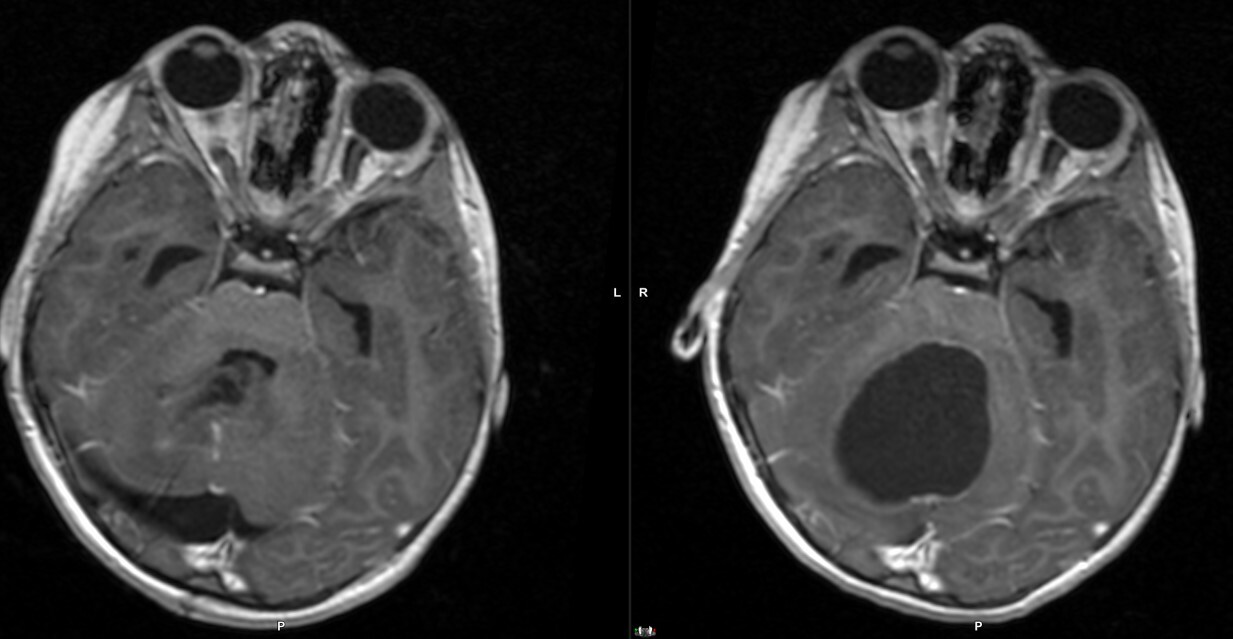

Η ασθενής υποβλήθηκε σε MRI εγκεφάλου, η οποία αποκάλυψε:

- Χωροκατακτητική εξεργασία στον οπίσθιο κρανιακό βόθρο.

- Σοβαρά πιεστικά φαινόμενα στην παρεγκεφαλίδα και το στέλεχος.

- Δευτεροπαθή αποφρακτικό υδροκέφαλο.